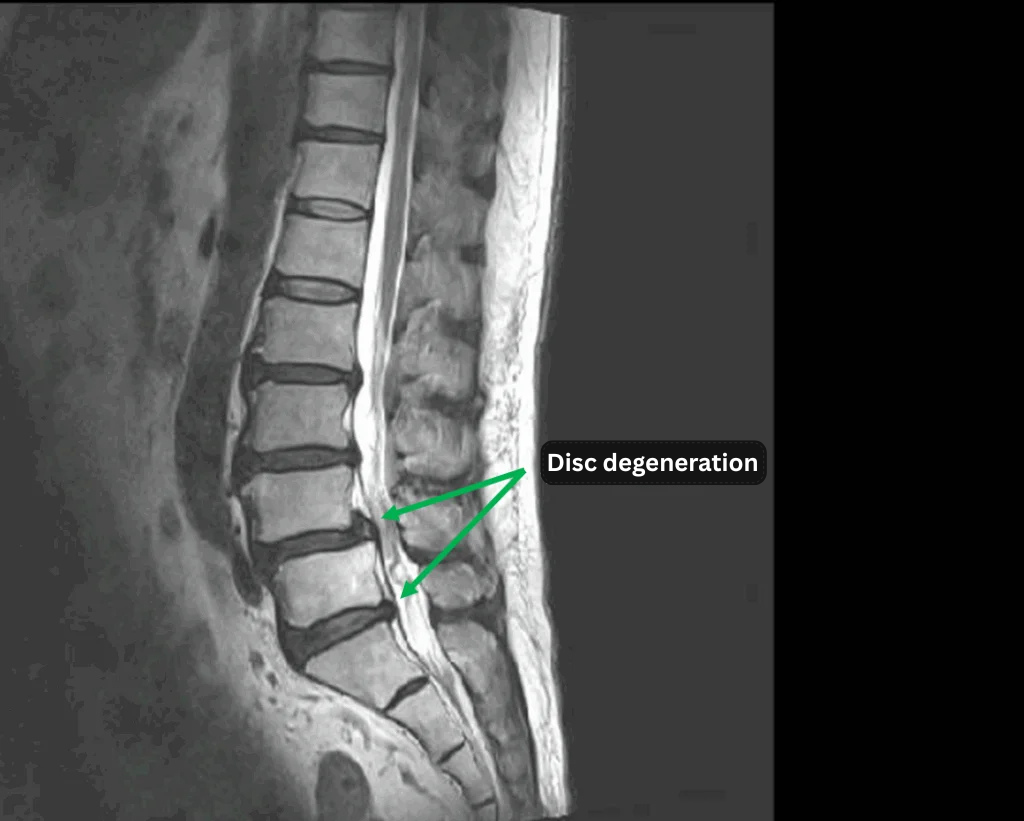

- L2/3, L3/4, L4/5, L5/S – Disc degeneration

- L4 – Anterior spondylolisthesisり

The above findings were also observed on the imaging.

・Foraminal stenosis caused by disc degeneration at L4/5 and L5/S is considered the main source of symptoms.